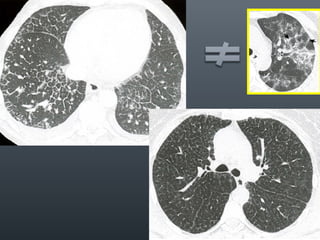

O documento discute vários conceitos radiológicos incluindo consolidação, atelectasia, nódulos, pseudocavidades e padrões intersticiais, fornecendo definições, sinais e diagnósticos diferenciais para cada tópico. Ele também discute a redução da atenuação pulmonar e fornece um link para mais informações.